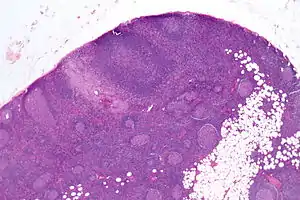

| Micrograph of a lymph node biopsy showing progressive transformation of germinal centres. H&E stain. | |

Microscopic appearance

PTGCs is characterized by:[1]

- follicular hyperplasia (many follicles),

- focally large germinal centres, with poorly demarcated germinal centre (GC)/mantle zone interfaces (as GCs infiltrated by mantle zone lymphocytes), and

- an expanded mantle zone.